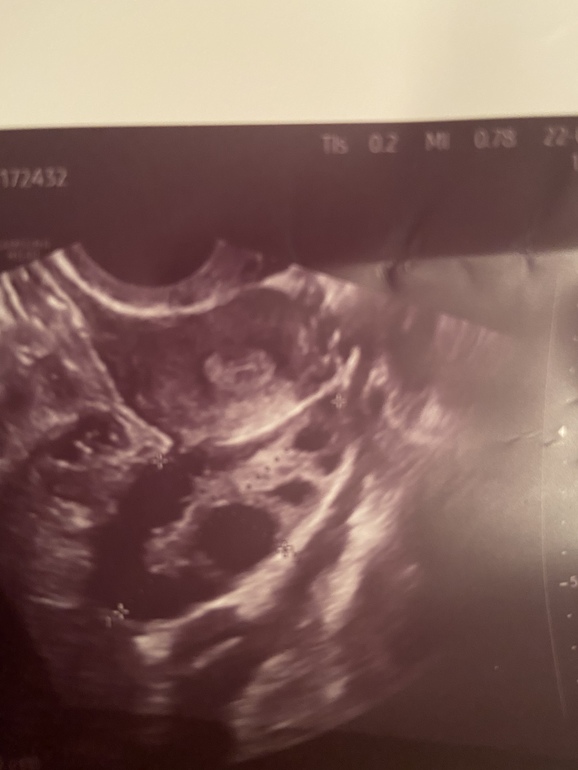

Фото узи. Неровные края.. может ЖТ?

Но как вам края фолликула? Или просто снимок размазался. Я дотошная. Завтра уже успокоюсь, но что думаете?

Фото ДФ 21 на 11 Дц

Судя по снимку это ЖТ. Фолик даже если он регресирует по другому выглядит. Да еще видно ведь что вокруг ЖТ есть ободок, у обычного фолика стенки тонкие. А жидкости может и не быть уже, тк она рассасывается в течении 1-4дней после овуляции.